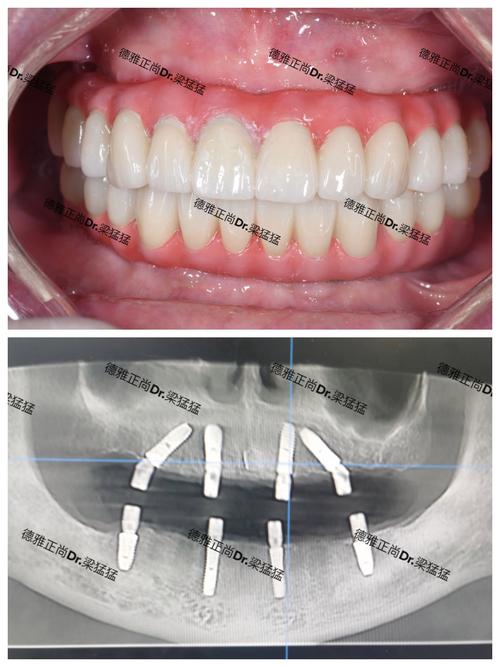

深圳南山区种牙的核心优势在于其优质的医疗资源与技术实力,区域内聚集了深圳市人民医院、北京大学深圳医院、南方医科大学深圳医院等三甲医院口腔科,以及瑞尔齿科、拜博口腔、马泷齿科等全国知名连锁口腔机构,还有众多本土口碑诊所,这些机构普遍配备数字化口腔设备,如CBCT(锥形束CT)、口内扫描仪、3D打印技术等,可实现种植术前精准评估、术中导航定位,大幅提升手术安全性与成功率,南山区的种植医生团队经验丰富,许多医生具备海外进修背景或公立医院从业经历,尤其在即刻种植、微创种植、全口/半口种植等复杂技术上具备成熟案例,能满足不同患者的修复需求。

南山区种牙流程通常分为术前检查、方案设计、手术实施、修复戴牙及术后维护五个阶段。术前检查包括口腔全景片、CBCT、血常规等,评估牙槽骨高度、密度及全身健康状况;方案设计是关键,医生会根据检查数据制定个性化方案,如选择种植体型号、是否需要植骨、采用微创或即刻种植等;手术实施一般在局部麻醉下进行,切口约3-4mm,植入种植体约需30分钟-1小时/颗,创伤小、出血少;修复戴牙在种植体与牙槽骨骨结合后(通常3-6个月),安装基台并取模制作牙冠,试戴调整后即可完成;术后维护需遵医嘱复查,注意口腔卫生,避免咀嚼过硬食物,种植牙使用寿命可达10-20年,甚至更长。